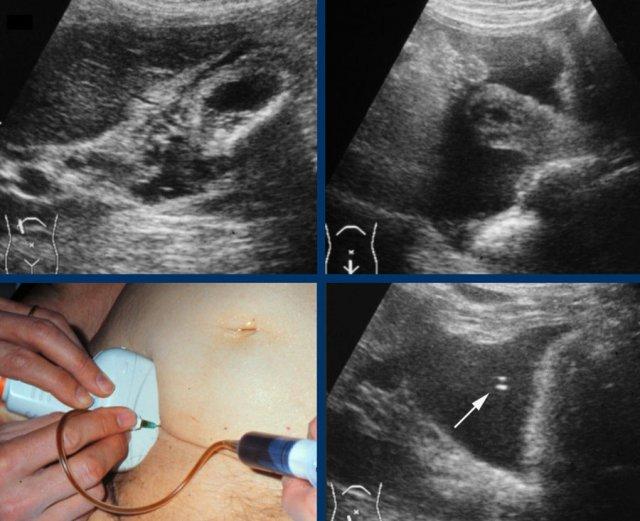

Hình ảnh siêu âm của một bệnh nhân bị phình to túi mật cấp tính, được khảo sát trên mặt phẳng dọc và mặt phẳng ngang.

Sỏi gây tắc nghẽn đang ở trạng thái kẹt (mũi tên).

Lưu ý rằng khi ấn đè, túi mật phình to phồng lên về phía thành bụng (đầu mũi tên), cho thấy áp lực trong lòng túi mật tăng cao.

Ở bệnh nhân này, khám siêu âm ở tư thế nằm nghiêng không thể xác định được sỏi gây tắc nghẽn do sự hiện diện của nhiều viên sỏi.

Nếu siêu âm ở tư thế đứng cho thấy tất cả các viên sỏi di động đã di chuyển xuống đáy túi mật, bệnh nhân được yêu cầu nằm xuống trở lại, ngay lập tức xoay sang bên trái.

Bằng cách này, các viên sỏi sẽ ở lại vùng đáy túi mật, giúp quan sát rõ hơn cổ túi mật và ống túi mật (hình).

Tất cả các viên sỏi đã di chuyển về phía đáy túi mật, ngoại trừ viên sỏi kẹt (mũi tên).

Có hình ảnh dày thành túi mật, gợi ý viêm túi mật đang tiến triển (CRP là 110).

Lưu ý rằng trong trường hợp mật đặc, nhớt, các viên sỏi có thể thay đổi vị trí rất chậm, đôi khi mất vài phút để di chuyển xuống điểm thấp nhất.

Dưới đây là hai ví dụ về sỏi kẹt được phát hiện trong cơn đau quặn mật ở các bệnh nhân khác nhau.

Ở tư thế nằm ngửa, một viên sỏi (mũi tên) được phát hiện tại cổ túi mật.

Sau khi đứng dậy, cúi người và đi lại, viên sỏi (mũi tên) không di chuyển xuống, do đó phải là sỏi kẹt.